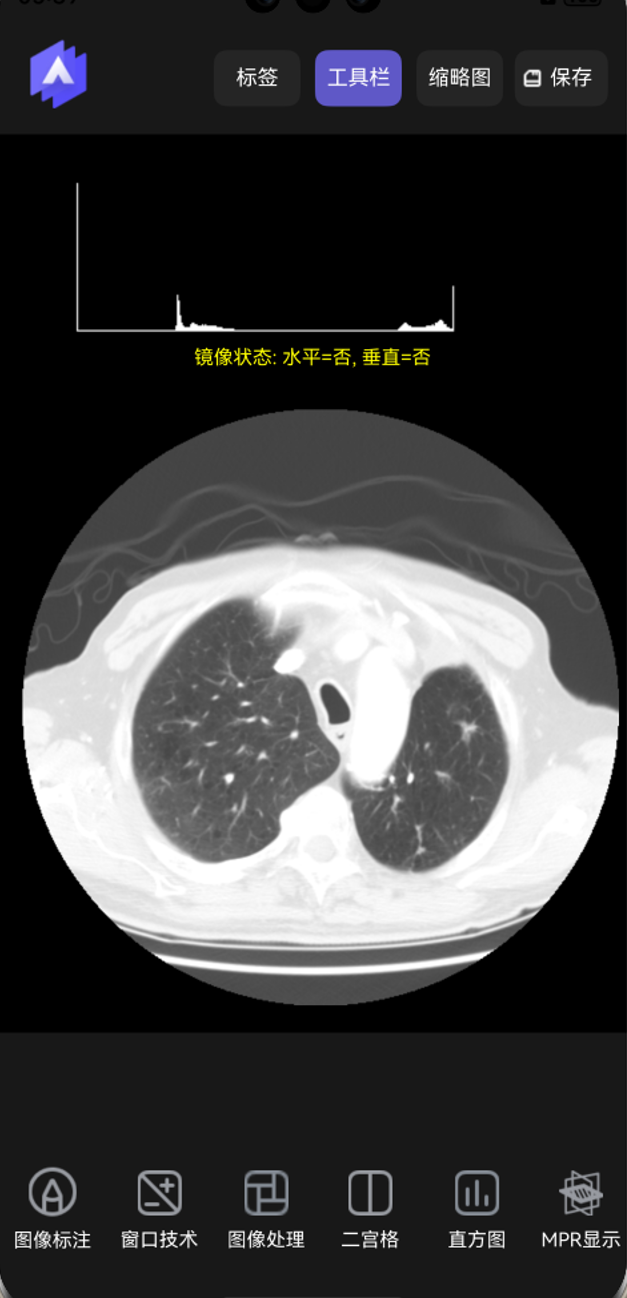

基本图像处理。提供了一套图像处理工具,可以进行旋转、水平镜像、垂直镜像及反色功能,如下图所示。